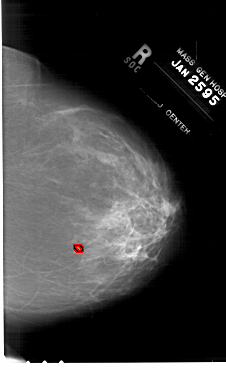

ics_version 1.0 filename A-1265-1 DATE_OF_STUDY 25 1 1995 PATIENT_AGE 48 FILM FILM_TYPE REGULAR DENSITY 3 DATE_DIGITIZED 23 7 1998 DIGITIZER HOWTEK 43.5 SEQUENCE LEFT_CC LINES 6556 PIXELS_PER_LINE 4111 BITS_PER_PIXEL 12 RESOLUTION 43.5 NON_OVERLAY LEFT_MLO LINES 6616 PIXELS_PER_LINE 4081 BITS_PER_PIXEL 12 RESOLUTION 43.5 NON_OVERLAY RIGHT_CC LINES 6646 PIXELS_PER_LINE 4066 BITS_PER_PIXEL 12 RESOLUTION 43.5 OVERLAY RIGHT_MLO LINES 6871 PIXELS_PER_LINE 3961 BITS_PER_PIXEL 12 RESOLUTION 43.5 OVERLAY |

FILE: A_1265_1.RIGHT_MLO.OVERLAY TOTAL_ABNORMALITIES 1 ABNORMALITY 1 LESION_TYPE CALCIFICATION TYPE PLEOMORPHIC DISTRIBUTION CLUSTERED LESION_TYPE MASS SHAPE IRREGULAR MARGINS ILL_DEFINED ASSESSMENT 4 SUBTLETY 3 PATHOLOGY BENIGN TOTAL_OUTLINES 1 BOUNDARY |